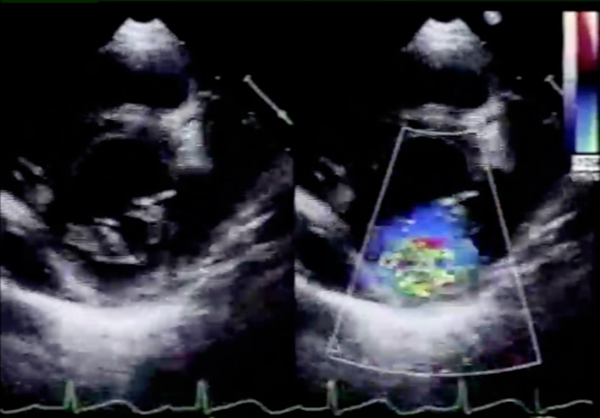

心臓超音波検査(Fig. 1)

Fig. 1 Preoperative echocardiogram of case 1

Moderate mitral valve regurgitation is shown. Posterior mitral leaflet, especially middle part (P2), is hypoplastic.

後尖,特にP2を中心とした低形成によるmoderate MRを認めた.僧帽弁輪径は20.0 mm(114% of normal)であった.